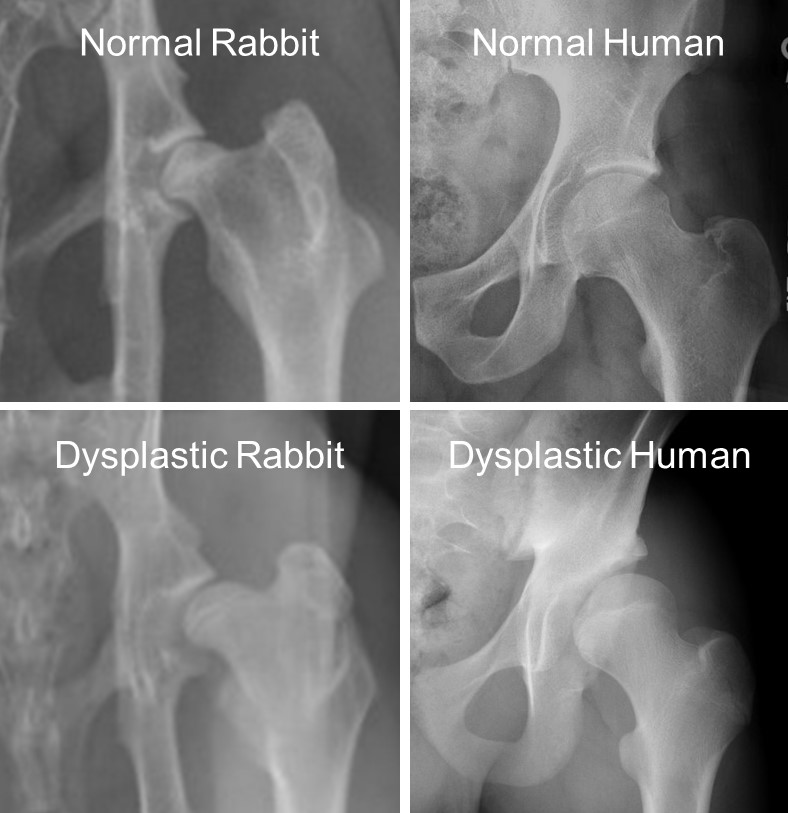

Preclinical Model of Young Adult Hip Dysplasia

This work aims to develop a skeletally mature preclinical model of hip dysplasia that can be used for systematic studies of research questions that cannot be ethically or effectively address with human studies. The model has previously been established for developmental dysplasia of the hip in young children, and is being extended to the context of skeletal maturity.

1. Fredericks DC, Rivas DJL, Cruse DC, Petersen EB, Holt JB, Willey MC, Goetz JE. Progressive degenerative cartilage changes with persistence of dysplastic deformity in rabbit hips. ORS 2026 Annual Meeting. March 27-31, 2026. Charlotte, NC. Poster #415: PS1-013 Hip-Structure, Function & Mechanics.